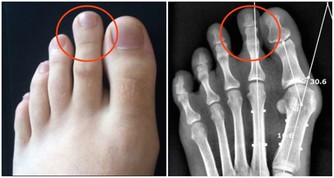

2、氣血不足

半夜3點到5點是器官正常的排毒時間,如果你常在這時間醒來,有可能是肺部氣血不足、流通不順暢,身體會開啟自愈模式,提醒你醒來,使得肺部器官不至於因氣血不足虛勞受到損害。